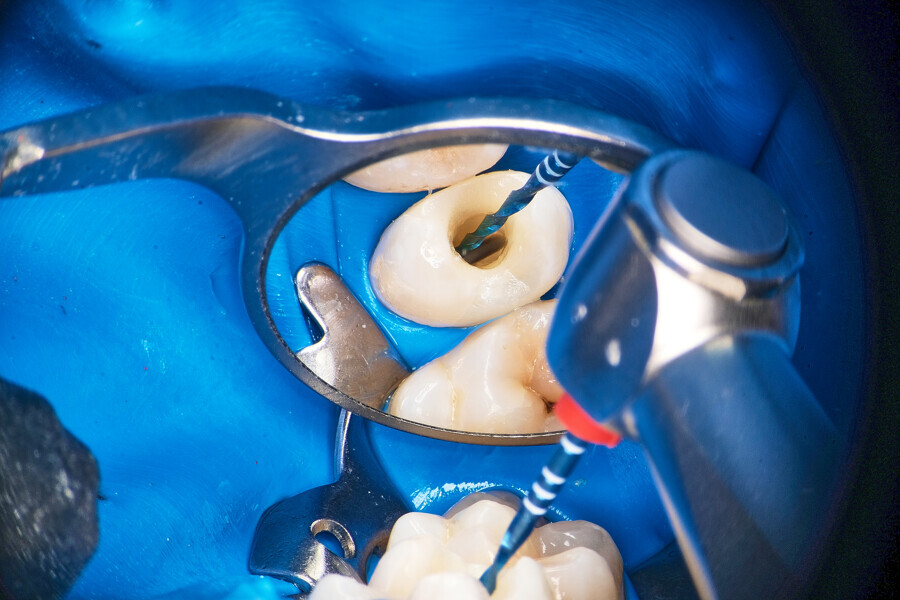

Case 2

The patient was referred to Dr Witkowski’s dental office for removal of a broken file in the mesial canal and the final endodontic procedure (Fig. 9). Owing to difficulties and the risk of perforation, bypassing of the file was suggested to the patient and she agreed. Proper instrumentation was performed in both the mesial and distal aspects using the R25 RECIPROC blue (VDW; Fig. 10). After this step, extensive irrigation protocol was performed with sonic agitation and continuous irrigation (Fig. 11). The root canal system was then prepared for obturation and obturated using the piston technique (Fig. 12). This technique is capable of obturating even not mechanically instrumented spaces and is very easy to use, especially when there is an obstacle in the canal space such as a broken file (Fig. 13).